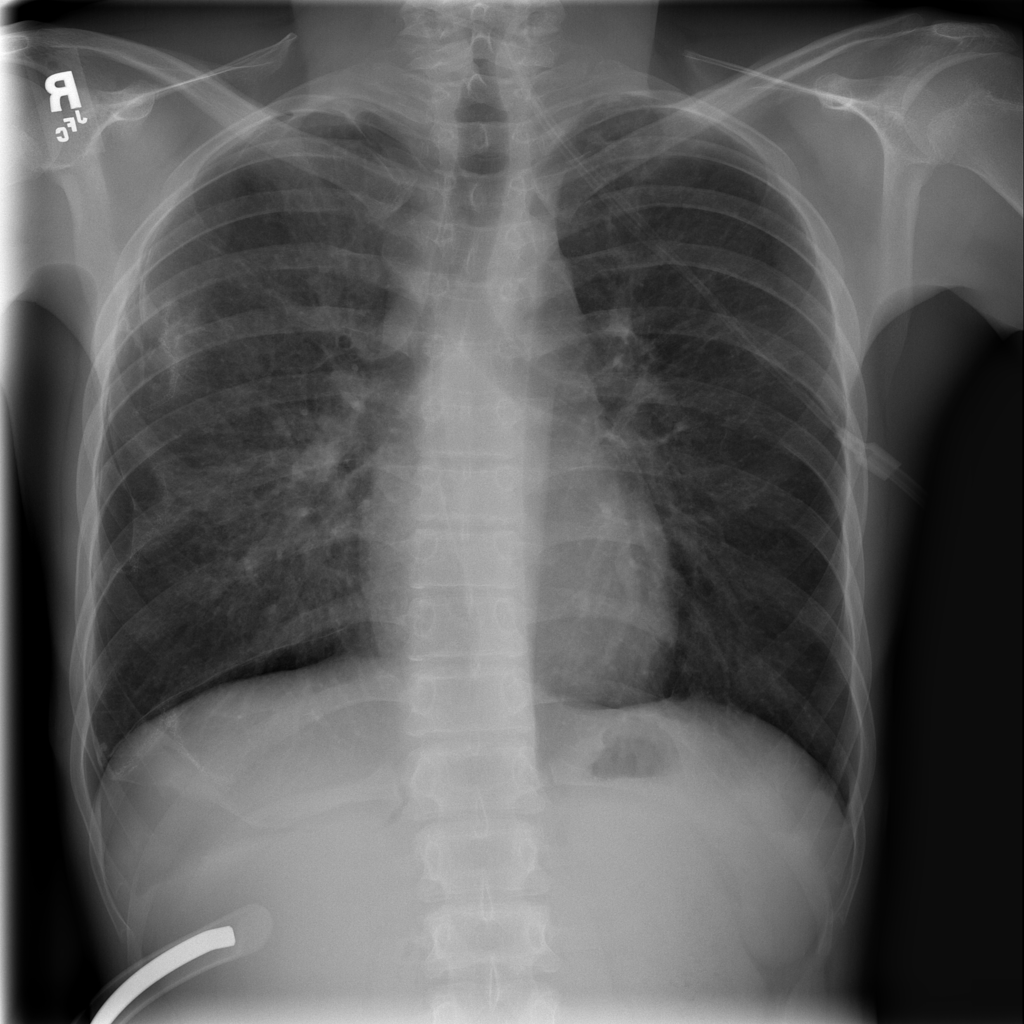

PAT-4639 · IMG-020Pneumothorax

PAT-4639 · IMG-020

PA